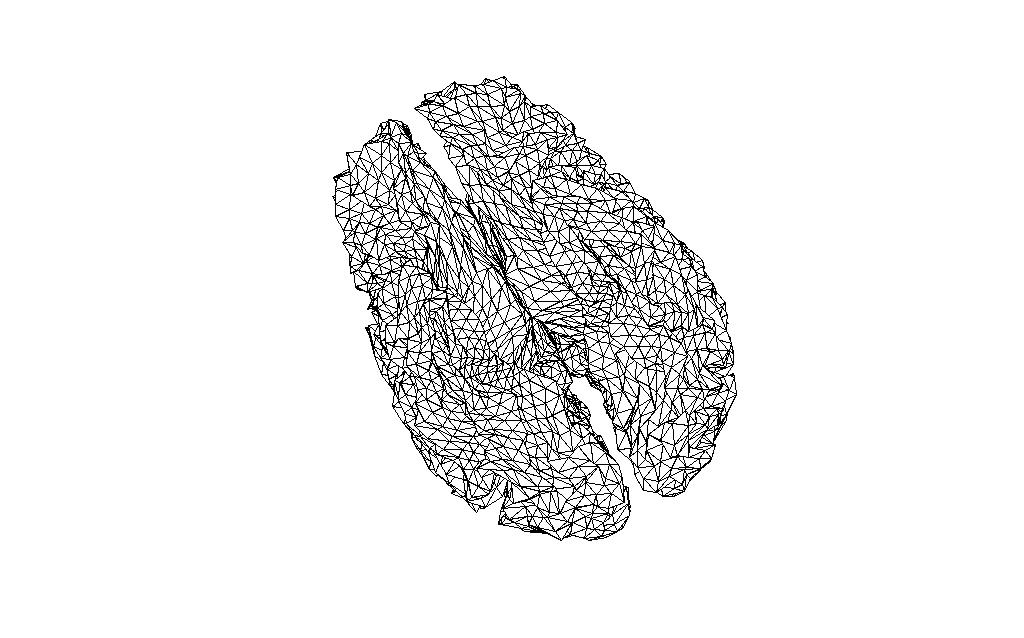

Comparing source spaces

I have read in the source space created on the sample data (subject 10 in Lin’s experiment) into MATLAB.

In MNE:

mne_setup_source_space --ico -6

In MATLAB:

src = mne_read_source_spaces('/<path>/sub10-oct-6-src.fif');

bnd_mne = [];

bnd_mne.pnt=[src(1).rr; src(2).rr];

bnd_mne.tri=[src(1).use_tris; src(2).use_tris + size(src(1).rr,1)];

figure;

ft_plot_mesh(bnd_mne)

And the source space of the same volume created in FieldTrip, and reduced to the same number of vertices with the MATLAB reducepatch function

bnd2_ft = bnd_ft;

[bnd2_ft.tri, bnd2_ft.pnt]=reducepatch(bnd_ft.tri, bnd_ft.pnt, 16384);

ft_plot_mesh(bnd2_ft);